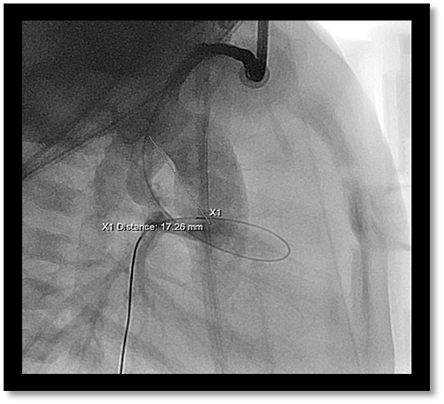

- Imaging: Initial biplane angiography; LAO 30° on the frontal and lateral 90° planes to delineate the course of the DA (Video 1) will provide a good initial assessment. Optimal angulated views may be supported by the pre-procedural CT. The goal is to outline the entire length and curvature of the DA. Multiple measurements including the shortest length connecting proximal to distal ends (Image 1) can be taken however predicting the optimal stent length can be challenging. Often crossing the DA with a coronary wire may lead to straightening of the ductus and assist in "predicting" the impact of a stent (Video 2). Some operators have used a coronary balloon to achieve the same goal.

Figure 1: Lateral angiographic image demonstrating straight measurement of PDA from aortic to pulmonary artery end. Exact length can be difficult to discern especially in a tortuous as demonstrated here.